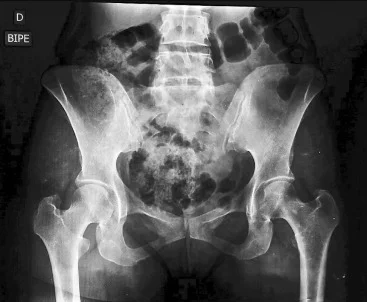

RADIOGRAFÍA DE PELVIS

La radiografía de pelvis es un examen de diagnóstico por imagen que emplea rayos X para generar una representación detallada de las estructuras internas.

Durante el examen de imagenología, un generador emite un haz de rayos X que atraviesa la pelvis. Los huesos, al ser más densos, absorben la radiación y aparecen en blanco, mientras que los tejidos blandos se muestran en tonos más oscuros.